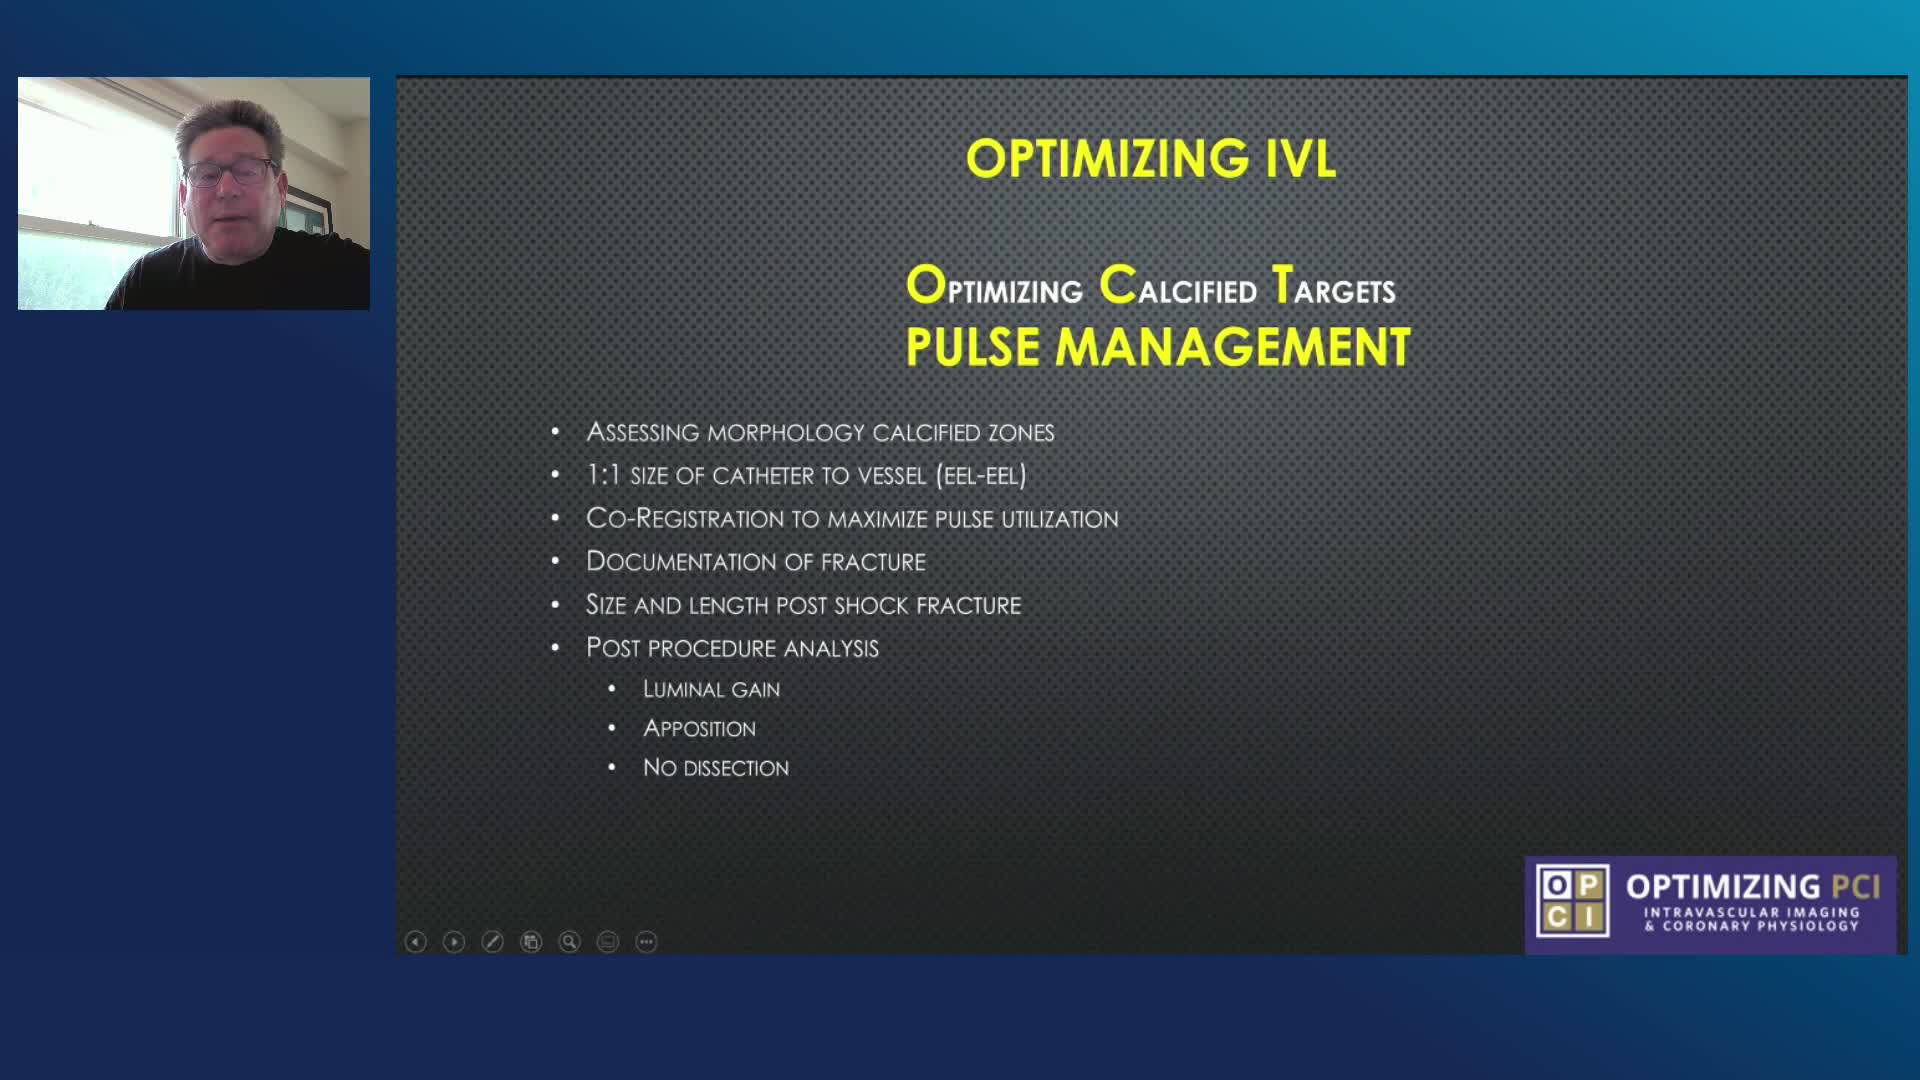

Coronary IVL Greatest Hits

Real-World EU Experience: Coronary IVL Across Different Calcium Morphologies from TCT 2022

Intravascular Lithotripsy for Treatment of Severely Calcified Coronary Artery Disease: The Disrupt CAD III Study

Shockwave IVL Coronary Real-World Cases, Outcomes & Algorithms: An InCathLab Webinar